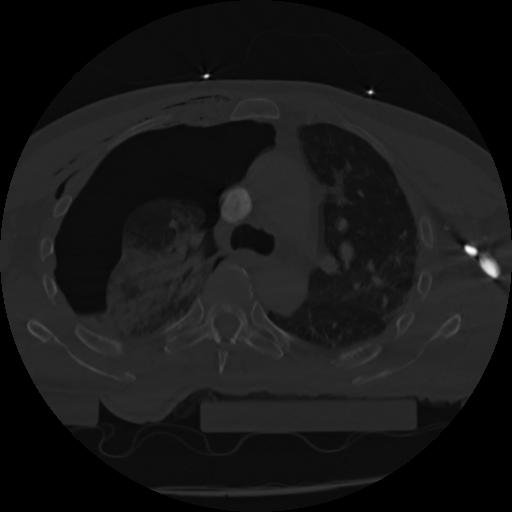

22 ANGIO,CE,Vol,0.5,ANGIO,,